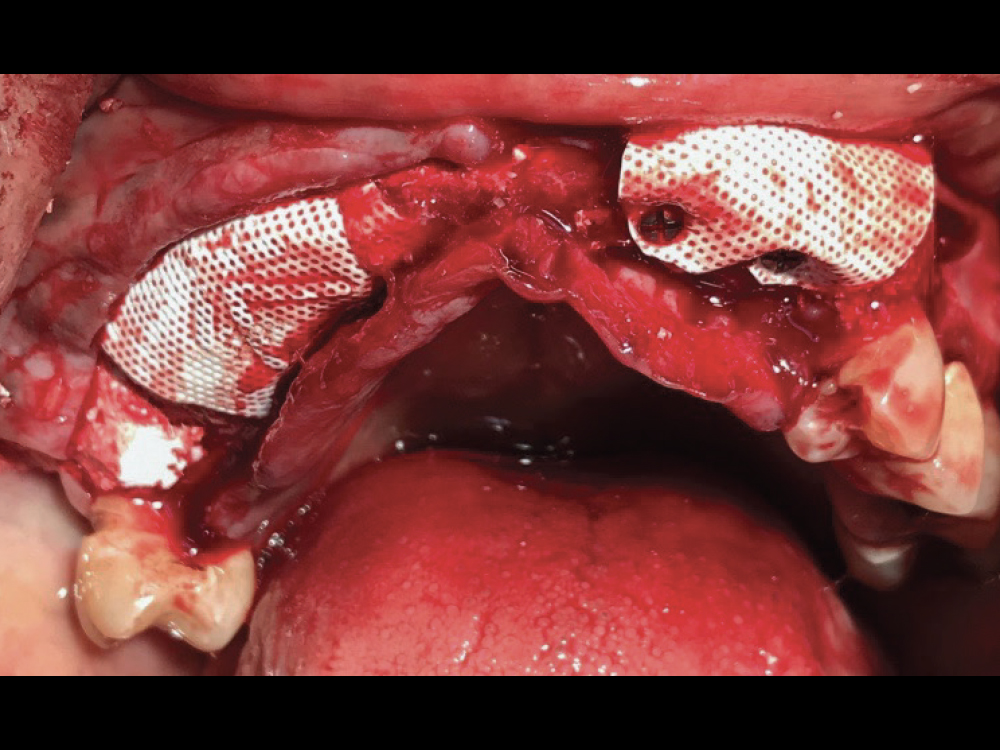

Figure 2: Treatment began with horizontal guided bone regeneration to widen the ridge between the patient’s healthy maxillary teeth. Alveoplasty was performed to level the bone, the ridge was grafted with a 50-50 blend of cortico-cancellous allograft and bovine-derived xenograft, and dense polytetrafluoroethylene (d-PTFE) membranes were positioned and held in place with fixation screws. The surgical flap was closed with interrupted sutures, and the patient left the appointment wearing a partial appliance, with a relieved intaglio surface in the grafted area.